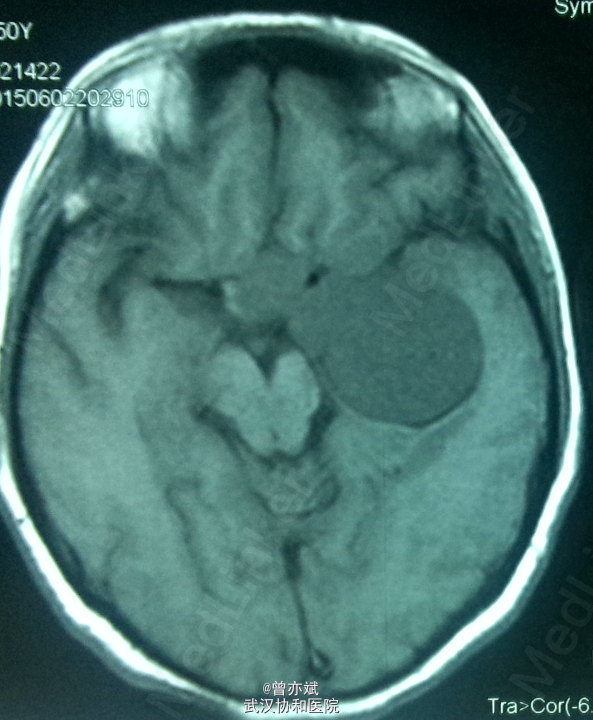

主诉:左眼视力下降十余年 简要现病史:患者10余年前出现左眼视力下降,当时未在意,近期右眼视力下降,行CT提示颅内占位。

查体:左眼视力0.8 颞侧偏盲,右眼视力 0.5 余无明显阳性体征。既往无特殊。 MRI: 稍长 T1,高flair信号,增强明显强化 ,其内点片状强化减低区。诊断:鞍区、中颅窝底巨大占位,考虑脑膜瘤可能性大。

诊断:脑膜瘤?海绵状血管瘤? 处理:手术切除 。

从 MRI上看,矢状位 增强可疑脑膜尾征,增强虽然明显但 不均匀 ,酷似脑膜瘤表现,手术中所见血供丰富,肿瘤实质多为血窦,考虑海绵状血管瘤。如果术前 能 诊断是海绵状血管瘤 ,是开颅手术还是分次伽马刀? 有大神指点一二不?